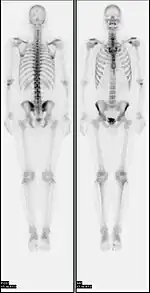

Bone scan showing multiple bone metastases from prostate cancer.